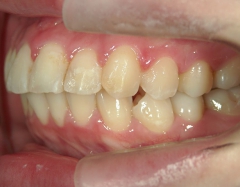

矯正歯科 治療後

no.6_8296_治療後_右.jpgno.6_8296_治療後_正面.jpgno.6_8296_治療後_左.jpg